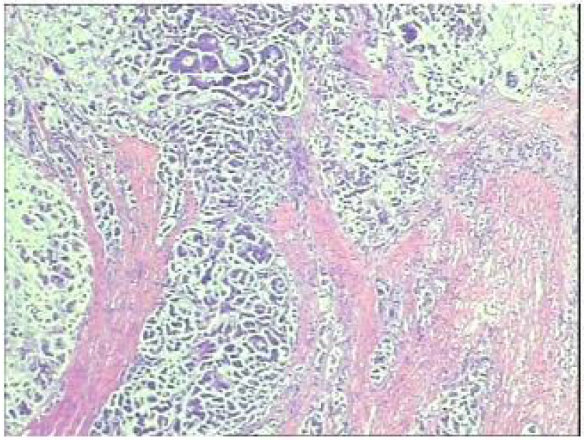

Q1 对于晚期转移性结直肠癌患者,目前,免疫治疗在新辅助治疗中的研究进展和临床应用如何? 结直肠癌是全球第三大肿瘤,转移性结直肠癌的5年生存率只有14%,治疗手段包括手术、化疗、放疗和靶向治疗等。免疫检查点抑制剂的出现也改写诊疗指南。大肠癌dMMR/MSI-H亚型约占所有病例的15%和mCRC病例的5%。由于dMMR/MSI-H的高突变率,肿瘤具有高免疫原性,使其能够激活免疫系统的抗肿瘤作用。 KEYNOTE-177这是一项三期国际开放标签随机对照研究,入选MSI-H/dMMR的IV期结直肠癌患者,比较帕博利珠单抗治疗(200 mg,每3周1次,最多35个周期)与在一线中使用或不使用抗VEGF或抗EGFR单克隆抗体的标准双药化疗,主要终点是PFS和OS。结果显示,帕博利珠单抗组患者的中位PFS时间为16.5个月 VS 8.2个月;3年PFS率分别为42% VS 11%,3年OS率分别为61% VS 50%。帕博利珠单抗组ORR为45.1%(20例完全缓解,49例部分缓解),化疗组为33.1%(6例完全缓解,45例部分缓解);帕博利珠单抗组83.5%的患者至少维持缓解了2年;在化疗组中,只有33.6%的患者缓解持续时间≥2年。KEYNOTE-177研究证实了帕博利珠单抗可以作为MSI-H或dMMR患者的一线标准治疗。 在2021版CSCO结直肠癌诊疗指南中,MSI-H结直肠癌姑息一至三线均推荐免疫治疗,其中帕博利珠单抗作为一线治疗的一级推荐;CheckMate-142研究选择MSI-H/dMMR转移性结直肠癌患者,单免后线vs双免后线vs 双免一线:ORR 39% vs 65% vs 71%,DCR 69% vs 81% vs 84%,一线双免完全缓解率为13%。结果说明双免好于单免,一线好于后线。CheckMate-142研究具有划时代意义,它将免疫治疗从后线前移到一线。 COMMIT研究是一项前瞻随机开放标签的三期临床研究,评估了阿特珠单抗单药治疗对比mFOLFOX6(氟尿嘧啶、奥沙利铂、亚叶酸钙)+贝伐珠单抗+阿特珠单抗一线治疗dMMR或MSI-H转移性结直肠癌的疗效和安全性,目前该试验还在进行中。未来该项研究的结果将回答对于MSI-H晚期结直肠癌,在一线免疫治疗的基础上联合化疗和抗血管靶向药物是否可以进一步提高免疫治疗的疗效。 CheckMate 8HW是另一项随机对照三期临床研究,在一线治疗dMMR或MSI-H转移性结直肠癌中,比较纳武利尤单抗单药、纳武利尤单抗联合伊匹木单抗以及研究者选择的化疗这3种方案的疗效。这项研究将头对头地比较对于MSI-H晚期结直肠癌双免联合是否优于单免的疗效。 Q2 对于MSI-H/dMMR型局部晚期结直肠癌(LACRC),新辅助免疫治疗探索的进展与应用前景如何?有哪些潜在预测疗效的生物标志物? 对于MSI-H/dMMR型局部晚期结直肠癌患者,新辅助免疫治疗可以在肿瘤手术前,提前使患者的免疫系统识别肿瘤细胞,从而使患者的免疫系统更好地产生免疫应答。目前结直肠癌新辅助治疗的探索均为二期研究,探索模式多为双免疫或免疫联合化疗方案,直肠癌多为免疫联合放化疗(同步或序贯)的模式。 NICHE研究是探索纳武利尤单抗联合伊匹木单抗用于Ⅰ-Ⅲ期结肠癌新辅助治疗的二期临床研究,研究共纳入40例结肠癌患者,其中21例为dMMR,20例为pMMR(1例患者同时为pMMR和dMMR),81%的dMMR患者和40%的pMMR患者为临床Ⅲ期结肠癌。患者在接受首次免疫治疗后不迟于6周内接受结肠癌手术,dMMR结肠癌缓解率100%,其中完全缓解的患者占60%,MPR为95%;pMMR治疗组27%的患者也对免疫治疗产生了良好的应答。 NICHE2研究,纳入更多患者,探寻非转移性dMMR结直肠癌患者双免治疗(伊匹木单抗+纳武利尤单抗)的疗效,主要终点为安全性,3年无病生存期。结果显示:MPR率95%,PCR率67%,中位随访13.1个月后没有患者出现疾病复发,毒性可耐受。 NCT04165772研究(前瞻性,单臂,Ⅱ期研究),Ⅱ期和Ⅲ期患者接受新辅助dostarlimab(多塔利单抗)共6个月,结果显示CCR率为100%。 PICC研究是特瑞普利单抗联合或不联合塞莱昔布新辅助治疗错配修复蛋白缺陷或微卫星高度不稳定的局部进展期结直肠癌的双臂随机Ⅱ期临床试验,结果显示完全缓解率高达88%,进一步表明dMMR结直肠癌免疫疗效惊人,潜在替代放化疗及手术。 对于MSI-H或dMMR结直肠癌,NCCN结直肠癌指南中,新辅助治疗增加纳武利尤单抗±伊匹木单抗或帕博利珠单抗单药方案;转化治疗可以选择双免疫或单免疫用药方案。 但并非所有患者都能从免疫治疗中获益,故筛选免疫治疗的疗效预测生物标志物将显得尤为重要。近年来研究主要集中在包括MSI-H、PD-L1过表达、TMB-H(TPS3645)、POLE或POLD1基因突变、PI3K/AKT/mTOR通路、新抗原(身份和数量)、免疫系统状态(免疫细胞特征、T细胞受体相关)等。 Q3 您如何看待对于临床中MSI-H/dMMR 转移性结直肠癌患者使用免疫治疗,部分患者仍然会出现耐药问题? Q4 晚期结直肠癌通常预后相对较差、患者生存期不长,依然是我国困扰结直肠肿瘤治疗的瓶颈问题,但有治愈的可能,此时临床医生制定正确合理用药方案尤为重要。今年上半年发布的CACA-RC指南推荐不适合强烈治疗患者应用曲氟尿苷替匹嘧啶片(TAS-102)联合贝伐珠单抗,作为晚期不可切除结直肠癌姑息一线治疗方案。请您谈谈该推荐治疗对我国晚期不可切除结直肠癌患者的临床治疗带来怎样的获益? 今年上半年CACA-RC指南推荐了不适合强烈治疗的患者应用TAS-102联合贝伐珠单抗作为不可切结直肠癌一线治疗方案,是在不可切除晚期结直肠癌一线治疗中石破天惊的一项突破。晚期mCRC的标准化疗方案在指南中是以奥沙利铂或伊立替康为基础的FOLFOX和FOLFIRI方案,在此基础上,可以根据基因分型联合西妥昔单抗或者贝伐珠单抗,但是依旧有部分患者身体状况无法耐受加强化疗,针对这一类患者的治疗方案选择非常有限,且预后情况并不理想。TAS-102+贝伐珠单抗治疗方案毒副反应相对较低,(临床试验提示比贝伐珠单抗联合卡培他滨效果好)疗效确切,在未来较长一段时间内,尤其是目前疫情肆虐,患者不方便住院治疗时,TAS-102可作为国内不适合强烈治疗的mCRC患者及老年患者的一线治疗优选方案,并为患者带来持续的、更优的生存获益。 二 病例分享 专家简介 王峰 教授 医学博士,副主任医师,硕士研究生导师 滨州医学院附属医院肿瘤科副主任 澳大利亚悉尼维斯迈医学中心访问学者 中华医学会放射肿瘤治疗学分会骨与软组织学组委员 中国临床肿瘤学会(CSCO)神经系统肿瘤专家委员会委员 山东省医师协会肿瘤精准医疗医师分会常务委员 山东省医师协会肿瘤放疗医师分会委员 山东省抗癌协会消化道肿瘤分会常务委员 山东省医学会咽喉肿瘤多学科联合委员会委员 山东省医学会烟草病学与戒烟多学科联合委员会委员 山东省健康管理协会消化道肿瘤防治分会常务委员 山东省医学会放射肿瘤学分会青年委员 山东省医学会妇科肿瘤多学科联合委员会委员 滨州市医学会放射肿瘤学专业委员会副主任委员 01 基本情况 (一)基本信息 患者男性,65岁,于2021-08-26第一次入滨州医学院附属医院风湿免疫科。 主诉:发作性右踝关节肿痛3年,再发1月。 查体:双足第一跖趾关节可见红肿,伴局部皮温升高。 既往史、个人史:既往脑梗死病史7年余,未遗留后遗症;有“膀胱结石”病史1年余,未系统诊治;有“痛风性关节炎”3年余,曾于滨州医学院附属医院风湿免疫科治疗。有高血压病史10年余,最高血压180/110mmHg,口服“吲达帕胺片”,血压控制可。 常规检查发现2次大便潜血阳性。 (二)辅助检查结果 1.肠镜检查 直肠、乙状结肠:直肠距肛门7cm可见一巨大溃疡型病变,表面溃烂,污秽苔,周边环堤样隆起,累及管腔1/3周圈,管腔无狭窄,于病变周边多点活检8块,质脆易出血;乙状结肠见一0.5cm*0.3cm息肉,余黏膜光滑,皱襞清晰,蠕动规律;肛管未见异常。降结肠、横结肠:横结肠见一0.3cm*0.4cm 0-IIa型息肉,表面粗糙,余黏膜光滑,血管纹理清晰,未见异常。 诊断:1.直肠Ca(进展期 溃疡型);2.结肠多发息肉——内镜下冷切除术+息肉摘除术。 2.胸部、上腹部未见明显异常。 直肠MR增强+DWI:直肠距肛缘约5.5cm处肠壁明显不均匀增厚,累及长度约6.0cm,呈等/长T1、等/稍长T2信号,T2压脂呈不均匀高信号,DWI呈高信号,ADC图信号减低,增强扫描呈明显不均匀强化,相应局部管腔狭窄,邻近浆膜面模糊,周缘可见小淋巴结。 02 治疗经过 2021-09-08:于全麻下行全直肠系膜切除+末端回肠预防造瘘术。 术中见:肝脏、胃、腹壁等无转移性结节。肿块位于腹膜返折处,活动度差,侵及浆膜。肠周见明显散在肿大淋巴结。 术后病理:直肠下段中分化腺癌,侵犯外膜下脂肪组织,肿瘤出芽分级(高级别,Bd3),侵犯神经侵犯,未见确切脉管内癌栓;两侧手术切缘、环周切缘及标记切缘内均未查见癌累及,肠周淋巴结内未查见转移癌(0/17)。pTNM分期:pT3N0Mx。免疫组化结果:CK(+),MSH2(+),MSH6(+),MLH1(+),PMS2(+),MDR-1(3+),HER2(3+),P53(3+),Ki-67阳性率约70%。 术后诊断: 1.直肠癌II(pT3NOMO)期术后; 2.结肠多发息肉术后; 3.痛风性关节炎; 4.高血压病(3级 很高危); 5.脑梗死。 CSCO指南: 2021-10-04至2022-06-03:FOLFOX方案化疗10周期(奥沙利铂150mg d1+氟尿嘧啶 0.7g d1+4.4g civ);术后预防性放射治疗DT5000cGy/25f,同步卡培他滨。 2021-11-25至2021-12-06:尿培养提示肺炎克雷伯菌感染,结合泌尿外科、感染科会诊意见,给予左氧氟沙星抗感染治疗。 2022-06-12 肺无法穿刺活检。 基因检测示:(直肠)KRAS/BRAF/NRAS/PIK3CA 基因均未检出突变。伊立替康UGT1A1基因检测结果:非风险基因型。 CSCO指南: 2022-06-20:西妥昔单抗联合FOLFIRI方案治疗(西妥昔单抗900mg d1,伊立替康320mg d1,氟尿嘧啶0.7g iv 4.3g civ)。 2022-07-06:骨髓抑制、腹泻,西妥昔单抗联合FOLFIRI方案治疗(西妥昔单抗900mg d1,伊立替康280mg d1,氟尿嘧啶0.7g iv 4.3g civ)。 疗效对比: 循证依据: C-TASK FORCE研究:首个证实TAS-102联合贝伐珠单抗治疗mCRC的疗效及安全性研究。TAS-102联合贝伐珠单抗是难治性mCRC患者潜在治疗选择,更多临床获益有待进一步研究。 TAS-102联合贝伐珠单抗治疗mPFS时间和mOS时间分别为5.6个月和11.2个月。 TAS-102联合贝伐珠单抗不良反应主要为血液学毒性。 日本大样本RWS:TAS-102和瑞戈非尼不同排序的回顾性研究。 日本大样本RWS:TAS-102单药较瑞戈非尼单药,可显著延长mOS,降低AE。 日本大样本RWS:两药序贯疗效优于单药,且≥65岁先用TAS-102获益更显著。 日本大样本RWS:TAS-102序贯瑞戈非尼组持续治疗时间更长。 2022-07-27至今 给予贝伐珠单抗联合TAS-102治疗期间复查CT评估SD,胃肠道反应不重,骨髓抑制Ⅰ度,耐受性尚可。 *本文仅代表专家观点,并经专家审校。